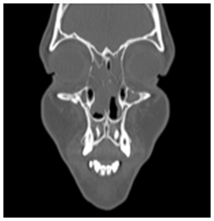

Almost all patients with PCD have a diagnosis of severe pansinusitis on Computed Tomography scan.6 Frontal and/or sphenoidal sinuses are hypoplastic or aplastic on 73% of the affected parienta. Therefore it is important to the diagnostic suspicion of PCD having a tomographic finding of aplasia or hypoplasia in the frontal and sphenoid sinuses (Figure 3).7

Figure 3 Sphenoidal aplasia.